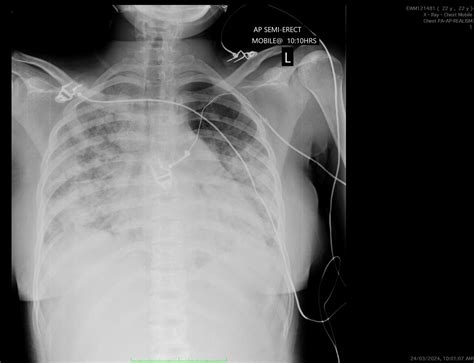

Diagnosis of Acute Chest Syndrome

Diagnosing Acute Chest Syndrome involves a combination of clinical evaluation and diagnostic tests. The key steps include:

• Chest X-ray to identify new infiltrates.